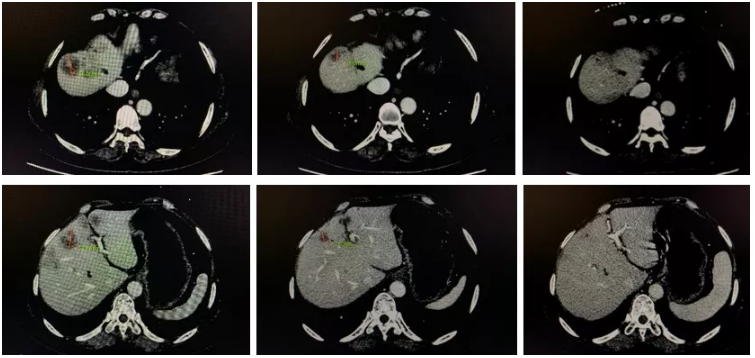

图2 患者二线治疗时肝转移灶影像学表现

(左:治疗基线2018-01,中:2018-03,右:2018-10)

图3 患者治疗流程图

(左:3周期治疗后,中:6周期治疗后,右:治疗后半年)